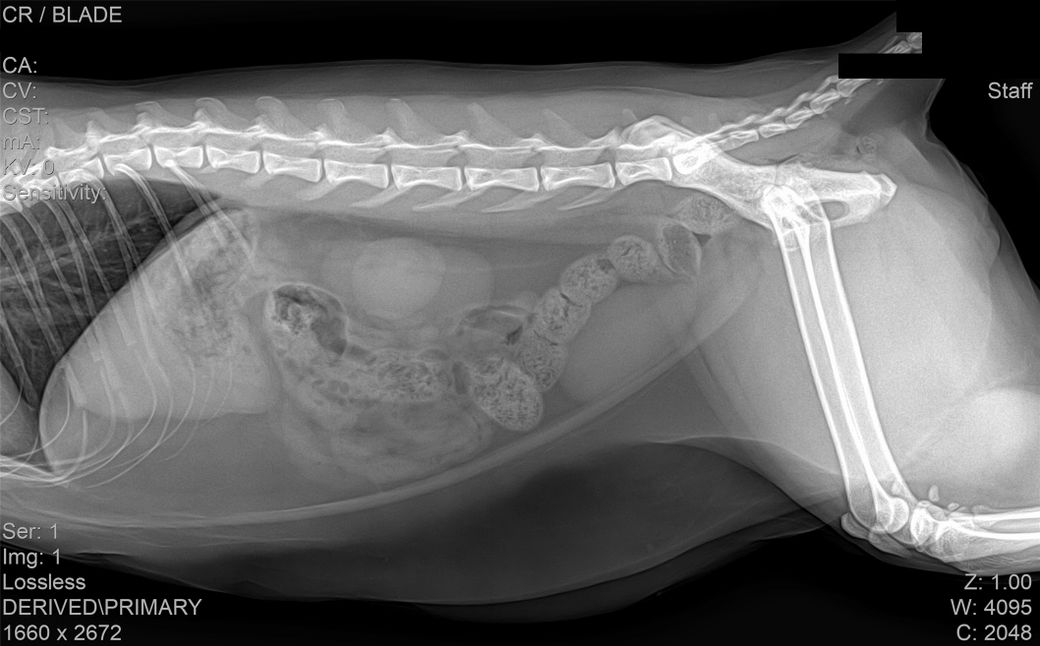

코숏 7살 고양이 HCM이 맞는걸까요?

건강검진 때 받은 사진입니다

건강검진 받은 병원에서는 따로 소견을 주지 않으셨으나 지인이 이 사진을 보고

자신의 첫째 고양이가 진단 받았었던 HCM과 엑스레이 사진이 유사하다는 말을 들어서요

HCM의 경우 방사선 상으로는 완전히 진단하는 것이 어렵습니다.

HCM이 심할 경우 심장 모양이 valentine shape으로 보이기도 합니다. 아무래도 수의사 선생님이 이런 양상으로 HCM 가능성을 말씀하신 듯하니 심장초음파 진료가 가능한 병원 가셔서 검사 해보시기 바랍니다.

HCM의 진단의 golden standard 는 심장초음파 검사입니다. 하지만 첨부된 자료에는 심장 초음파 검사 결과가 없고

흉부 방사선 검사 또한 외측상이 결여되어 있어 자료로 판단할 수 없습니다.